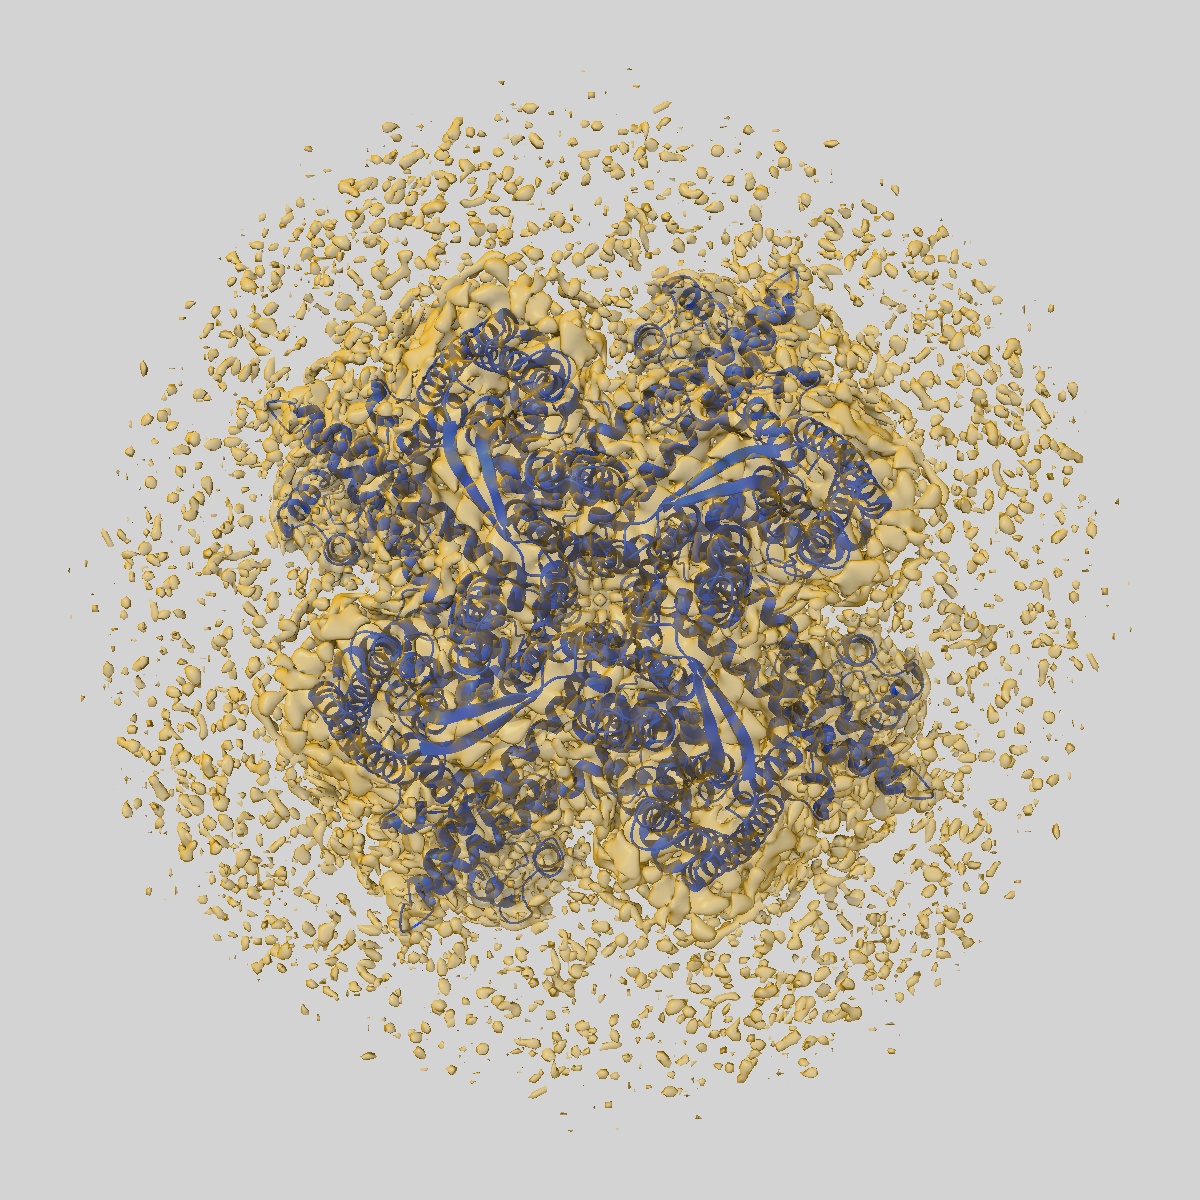

Cryo-EM structure of KCa2.2_II/calmodulin channel in complex with rimtuzalcap

Sample: RatKCa2.2_II/calmodulin channel in complex with rimtuzalcap

Fitted models: 9o93

Structural basis for the subtype-selectivity of K Ca 2.2 channel activators.